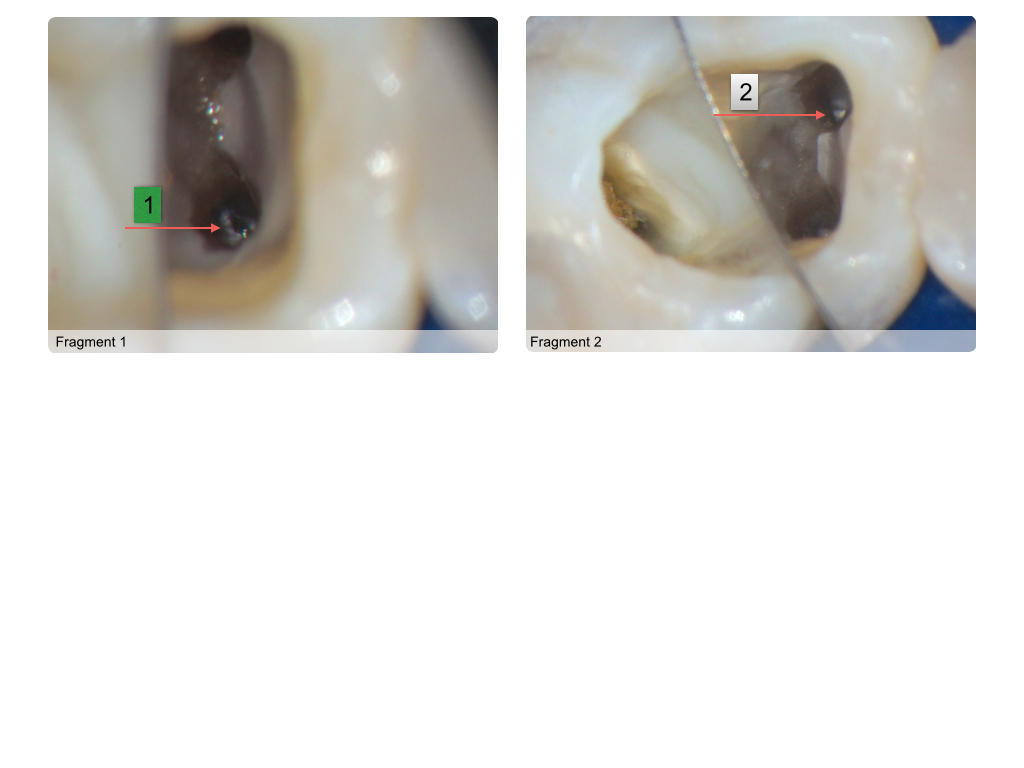

Instrumentenfrakturen (1)